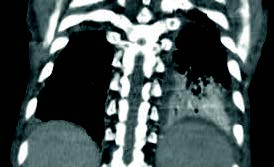

En el TAC torácico se aprecia: con anestesia local, se realiza exéresis ganglionar en lado derecho e inferior cervical para descartar linfoma versus metástasis.

Diagnóstico anatomopatológico: Ganglio linfático cervical: hematopoyesis extramedular con predominio de megacariocitos en relación con la mielofibrosis diagnosticada previamente. Linfadenitis por Mycobacterium tuberculosis. Ante una adenomegalia se debe realizar un diagnóstico diferencial, con analíticas y serologías virales, prueba de la tuberculina, Rx tórax, posteriormente con ecografías y PAAF (puncion aspiración con aguja fina), finalmente puede ser necesario un TAC o exéresis del ganglio para biopsia.

FIGURA 1